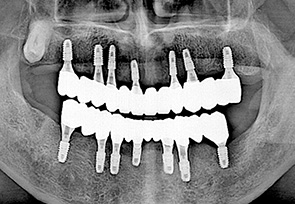

before

after